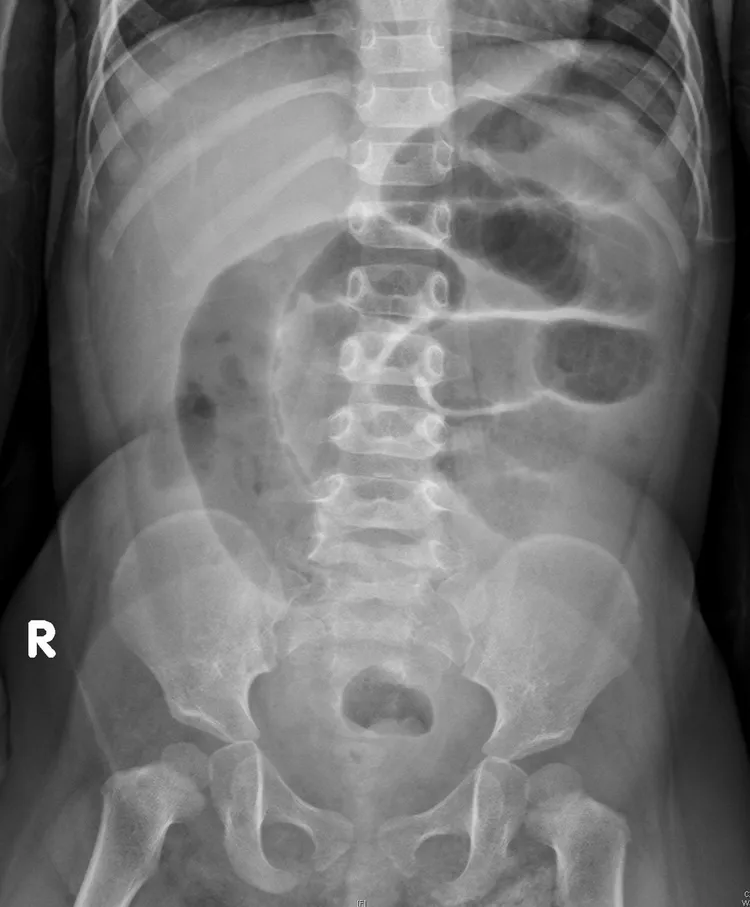

經安排X光、電腦斷層等檢查,賴宛孜發現男童小腸有多段腫脹現象,會小兒外科醫師蔡逸文為男童開刀。蔡逸文指,經剖開男童小腸段,發現裡面有多顆脹大的水晶寶寶,已將小腸阻塞,其中最大一顆橢圓形水晶寶寶,竟然有2乘以3公分大,這是男童為何會嘔吐、吃不下原因,取出腸內異物後,留男童住院觀察。

男童術後一度可進食,但2、3天後,又開始嘔吐、吃不下,賴宛孜再為男童檢查,發現還有水晶寶寶阻塞住腸道,因此在術後第5天,由蔡逸文再為男童開第2次刀。

蔡逸文說,腸阻塞患者因腸塞住,先是嘔吐、吃不下,可能脫水休克,若不治療,腸道接著可能發黑、壞死,甚至是破裂,引發腹膜炎與敗血性休克,是致死率高的急症。